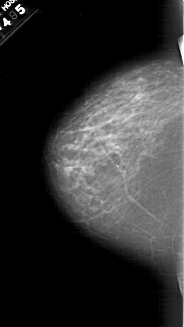

A_1467_1.LEFT_CC

LEFT_CC LINES 6196 PIXELS_PER_LINE 3496 BITS_PER_PIXEL 12 RESOLUTION 43.5 NON_OVERLAY